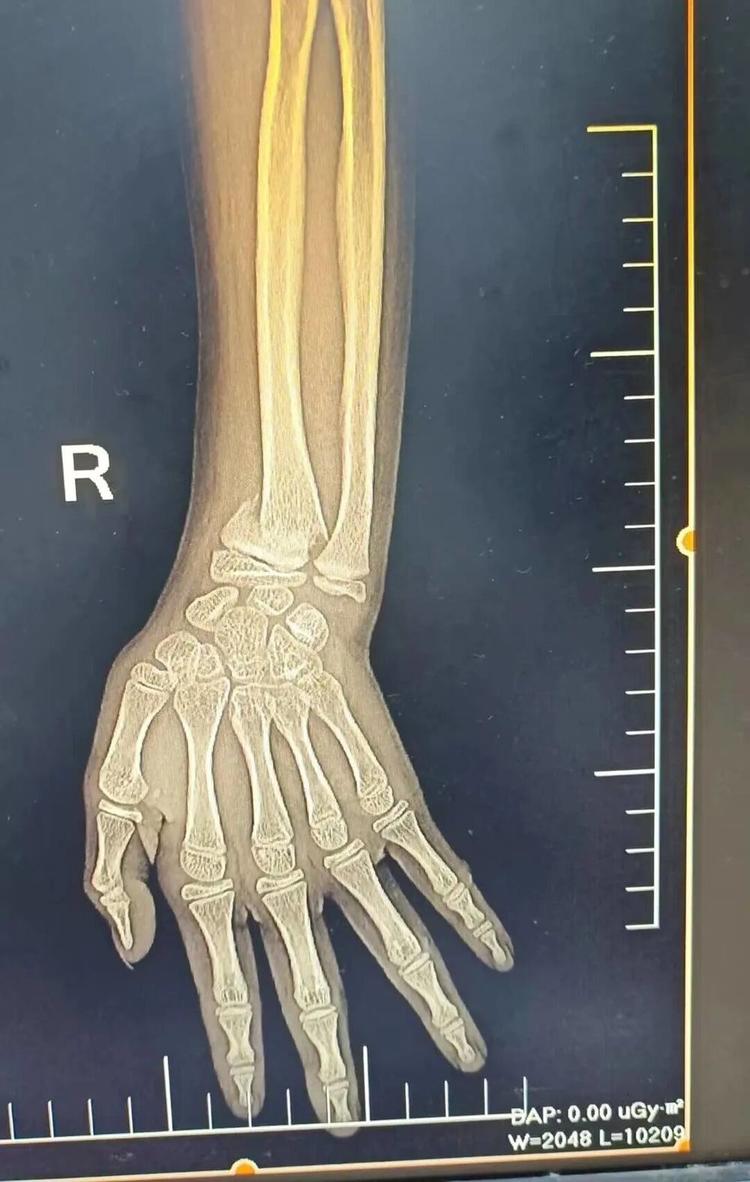

患者李某因意外造成桡骨远端骨折,若复位不佳,极易遗留腕关节畸形、疼痛无力等后遗症。来到益民中西医结合诊所后,通过陈氏正骨手法配合外用药治疗,复位效果理想。

▲治疗前后对比